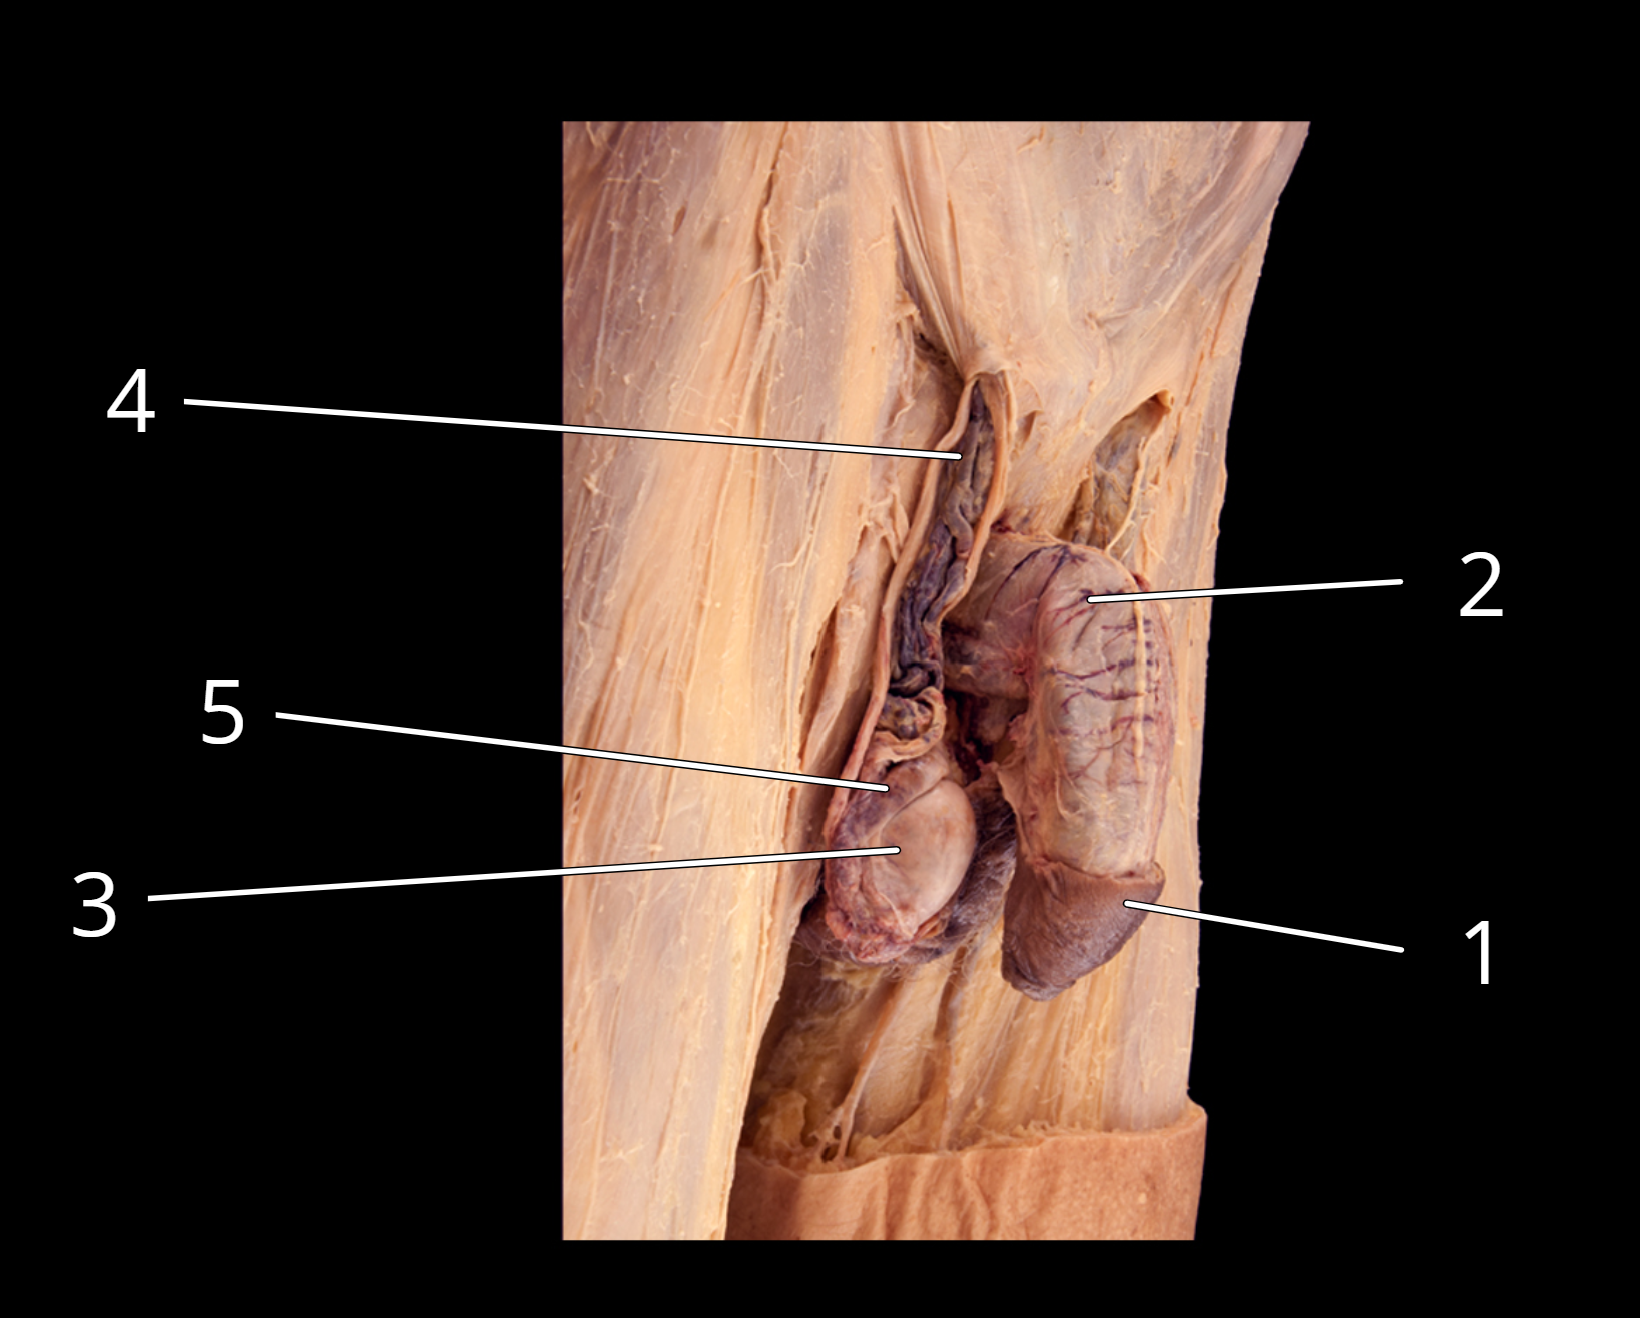

Penis and testis, lateral view

1. Prepuce

2. Penis

3. Tunica albuginea of testis

4. Testicular artery and pampiniform plexus of veins

5. Epididymis